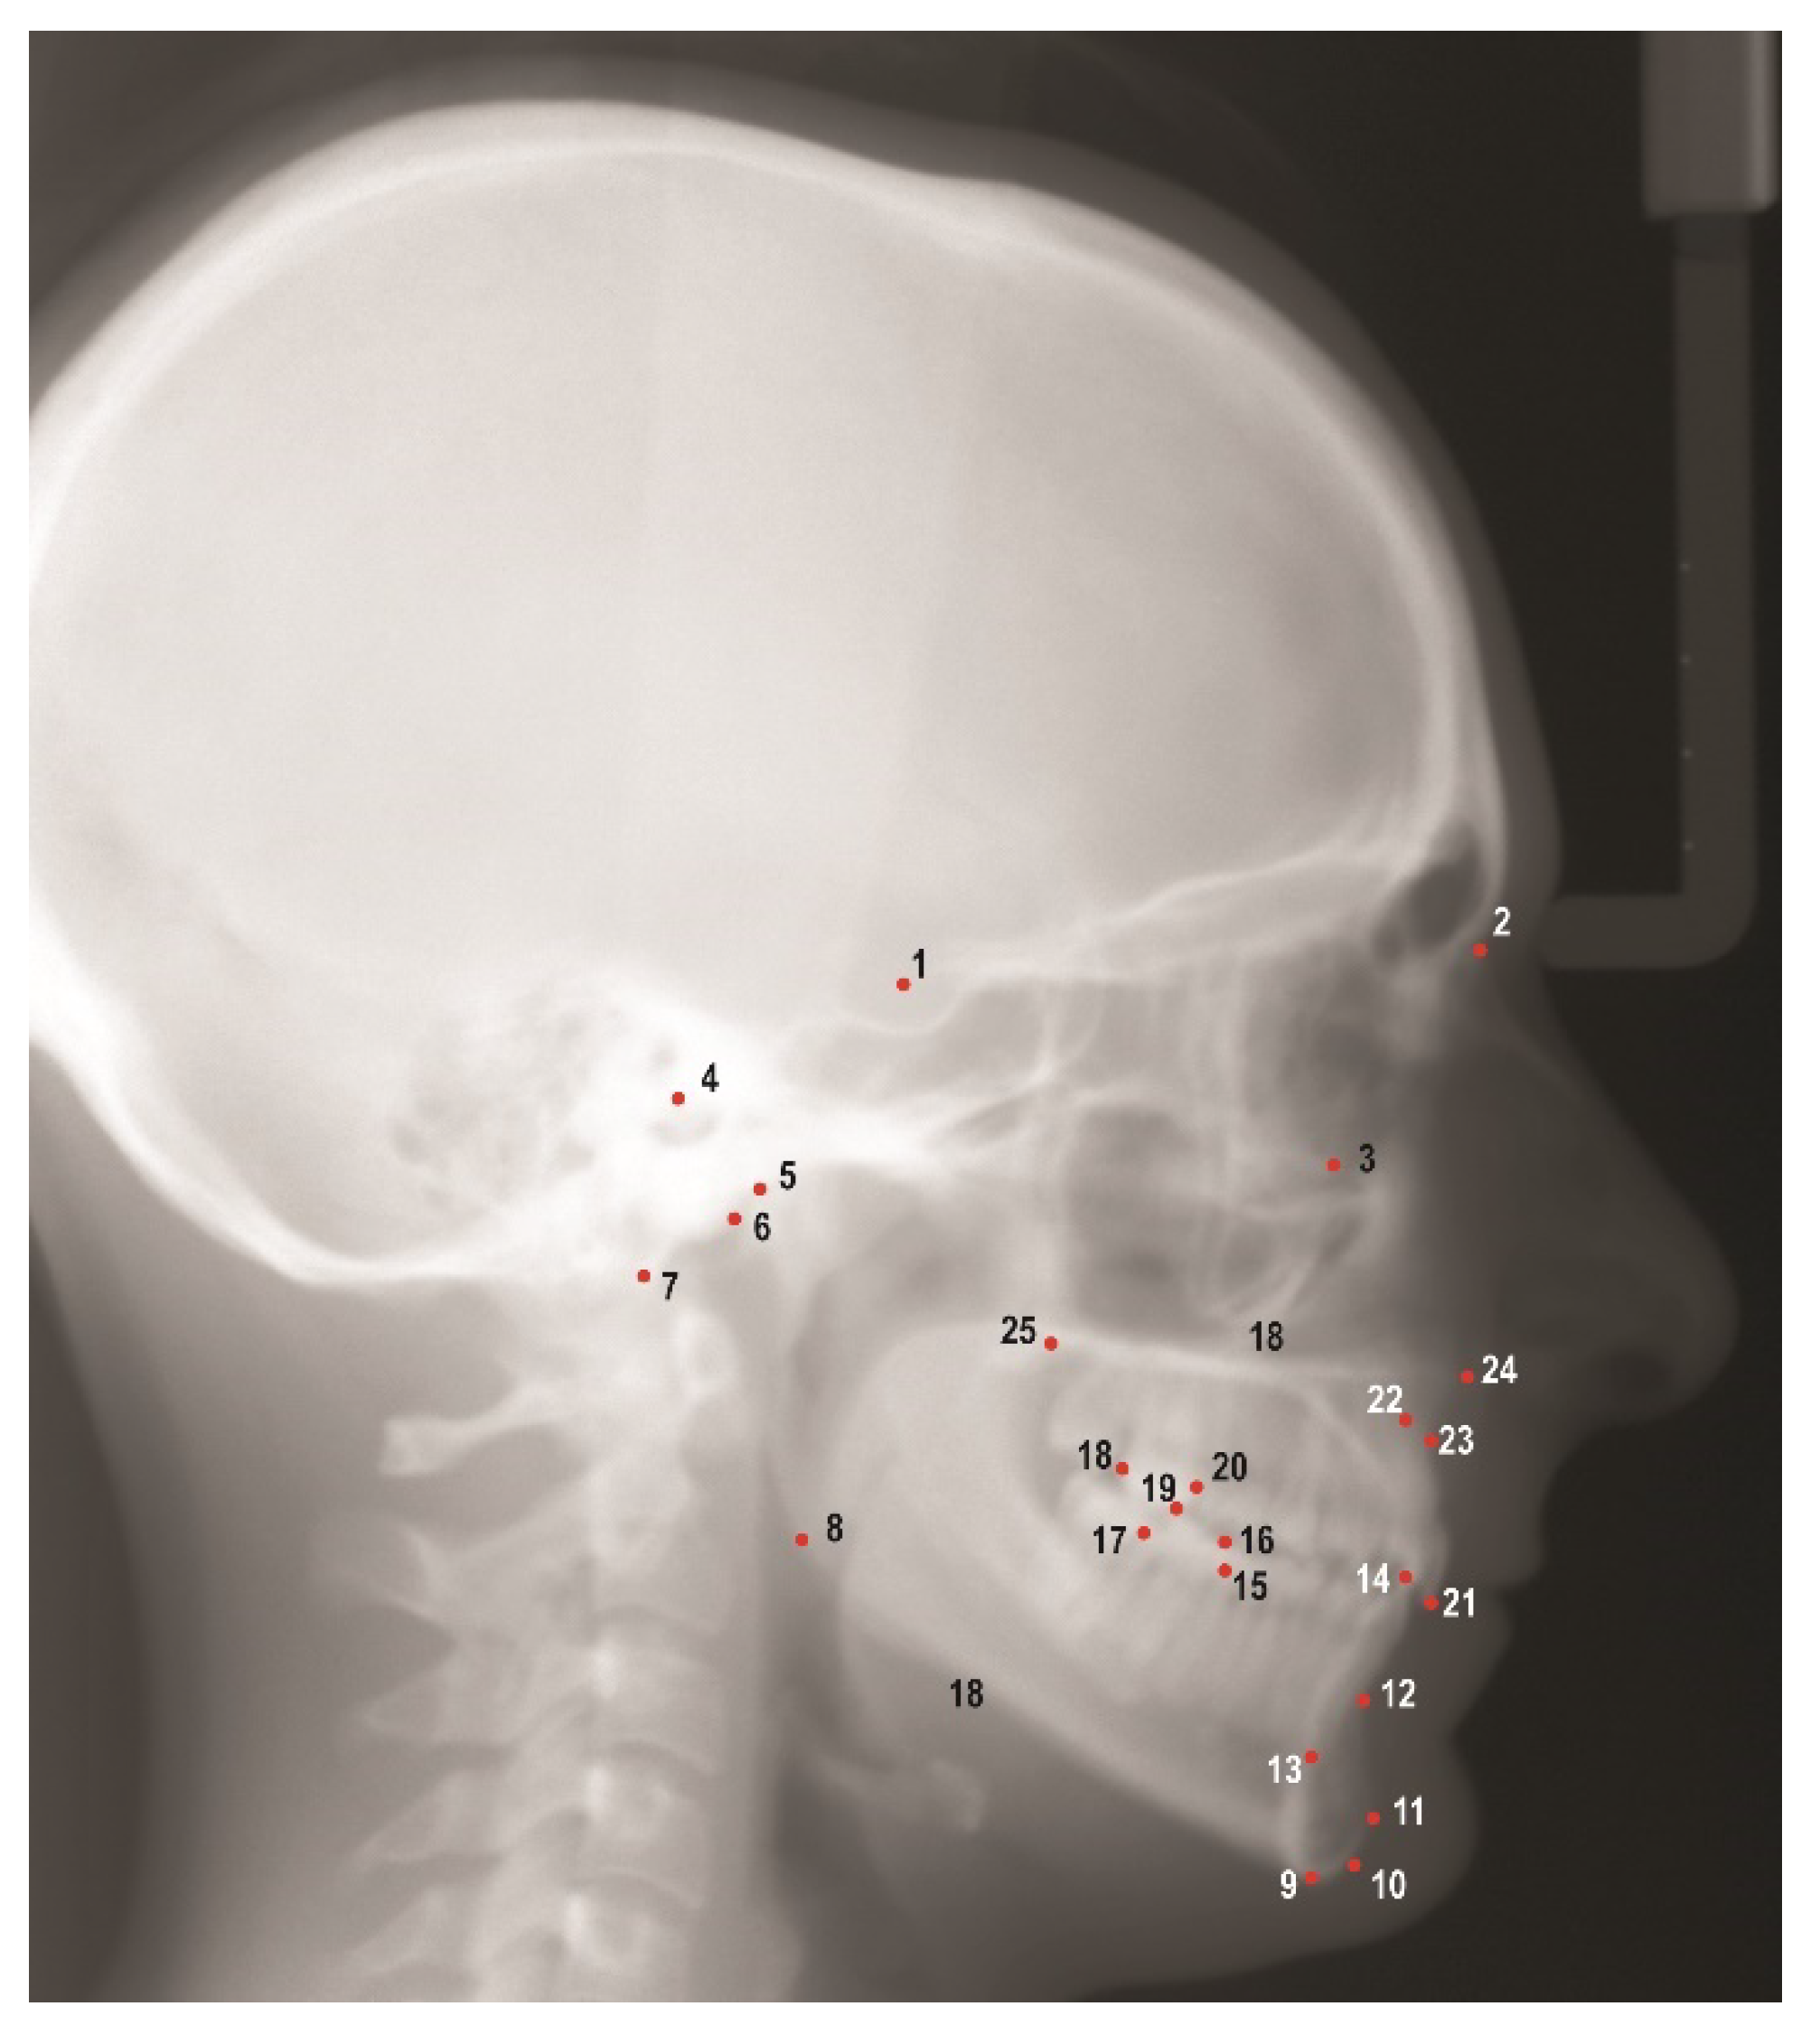

Images obtained from the AAOF collection were then imported into Dolphin Imaging V. 11.95 (Dolphin Imaging and Management Solutions, Chatsworth, CA, USA) for further analyses. A solitary investigator (G.Z.) identified and marked 25 hard tissue landmarks on each image (Figure 1), thereby enabling the calculation of 38 linear and angular measurements (Table S1). Several cephalograms did not show adequate soft tissue therefore, soft tissue landmarks and associated cephalometric measurements were not included in the study.

Figure 1. Cephalometric landmarks used in this study. 1. Sella (S), 2. Nasion (N), 3. Orbitale (Or), 4. Porion (Po), 5. Condylion (Co), 6. Articulare (Ar), 7. Basion (Ba), 8. Gonion (Go), 9. Menton (Me), 10. Gnathion (Gn), 11. Pogonion (Pog), 12. B point (B), 13. Lower incisor root apex (L1a), 14. Lower incisor incisal edge (L1i), 15. Mesial of lower first molar (L6m), 16. Mesiobuccal cusp of lower first molar (L6mb), 17. Distal of lower first molar (L6d), 18. Distal of upper first molar (U6d), 19. Mesiobuccal cusp of upper first molar (U6mb), 20. Mesial of upper first molar (U6m), 21. Upper incisor incisal edge (U1i), 22. Upper incisor root apex (U1a), 23. A point (A), 24. Anterior nasal spine (ANS), 25. Posterior nasal spine (PNS).